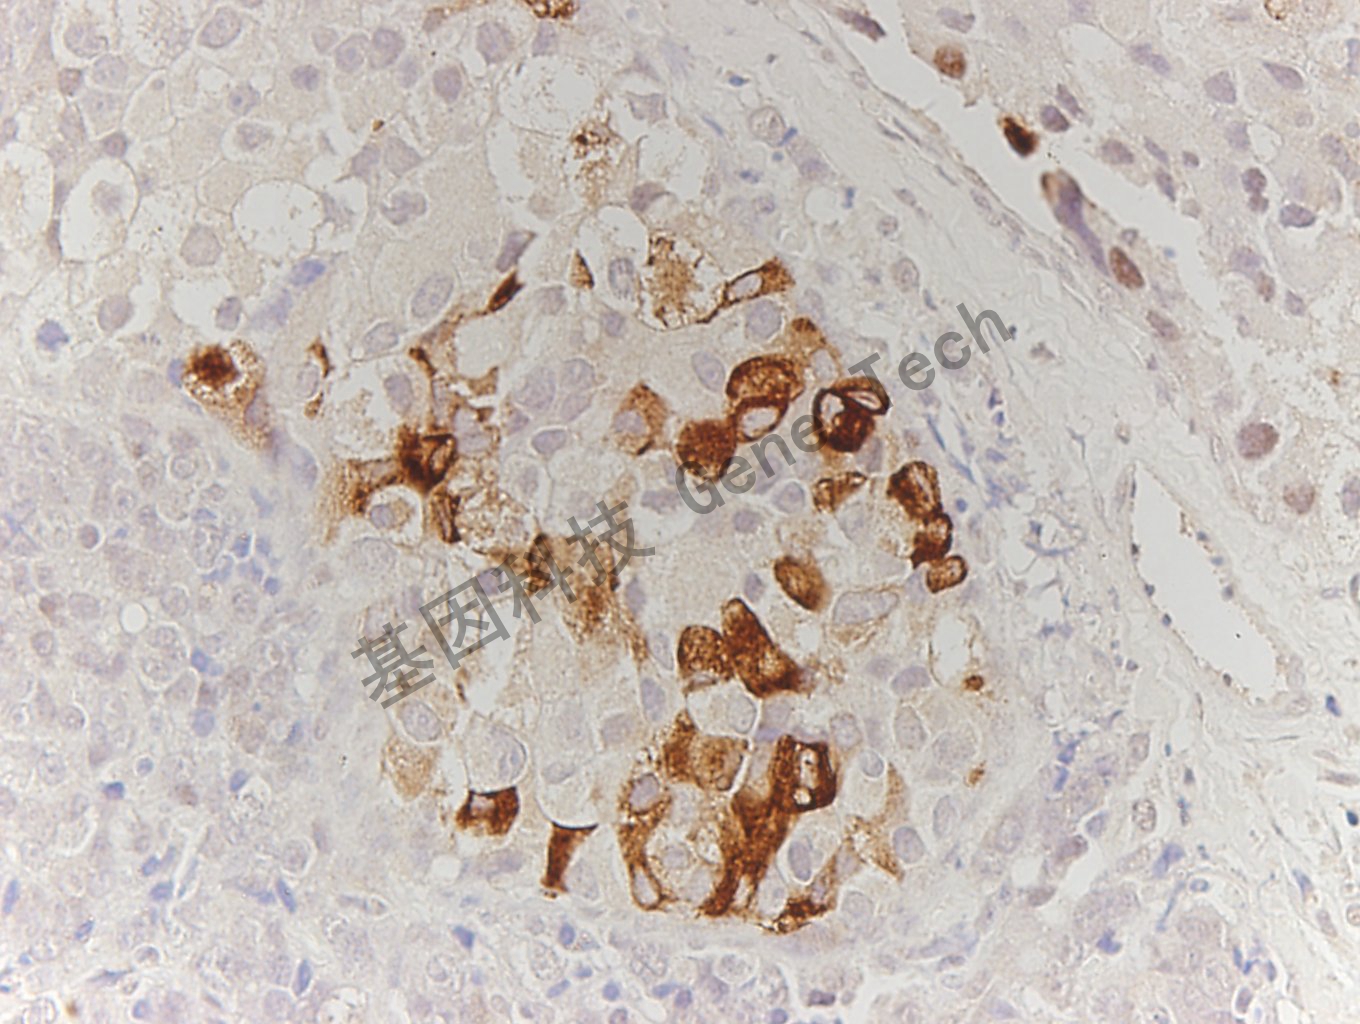

| 簡介:pS2亦稱PNR-2,是受雌激素調(diào)節(jié)的胞漿型多肽,分子量為6.5kDa。正常胃粘膜、小腸粘膜和乳腺上皮均有pS2的表達。腫瘤組織中主要表達于乳腺癌和胃癌,pS2在乳腺癌中的表達與ER表達相關,多見于ER、PR陽性的乳腺癌??捎糜谌橄侔┎∪藢?nèi)分泌治療反應的研究。 | ||

| 乳腺癌石蠟切片,用 PS2(GT2023)染色,細胞漿陽性,DAB 顯色。 | ||